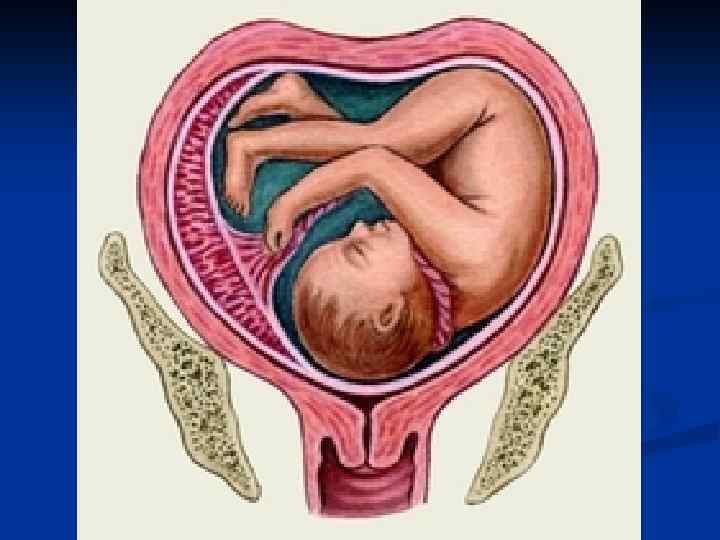

Женские половые органы, organa genitalia feminina

Женские половые органы, organa genitalia feminina